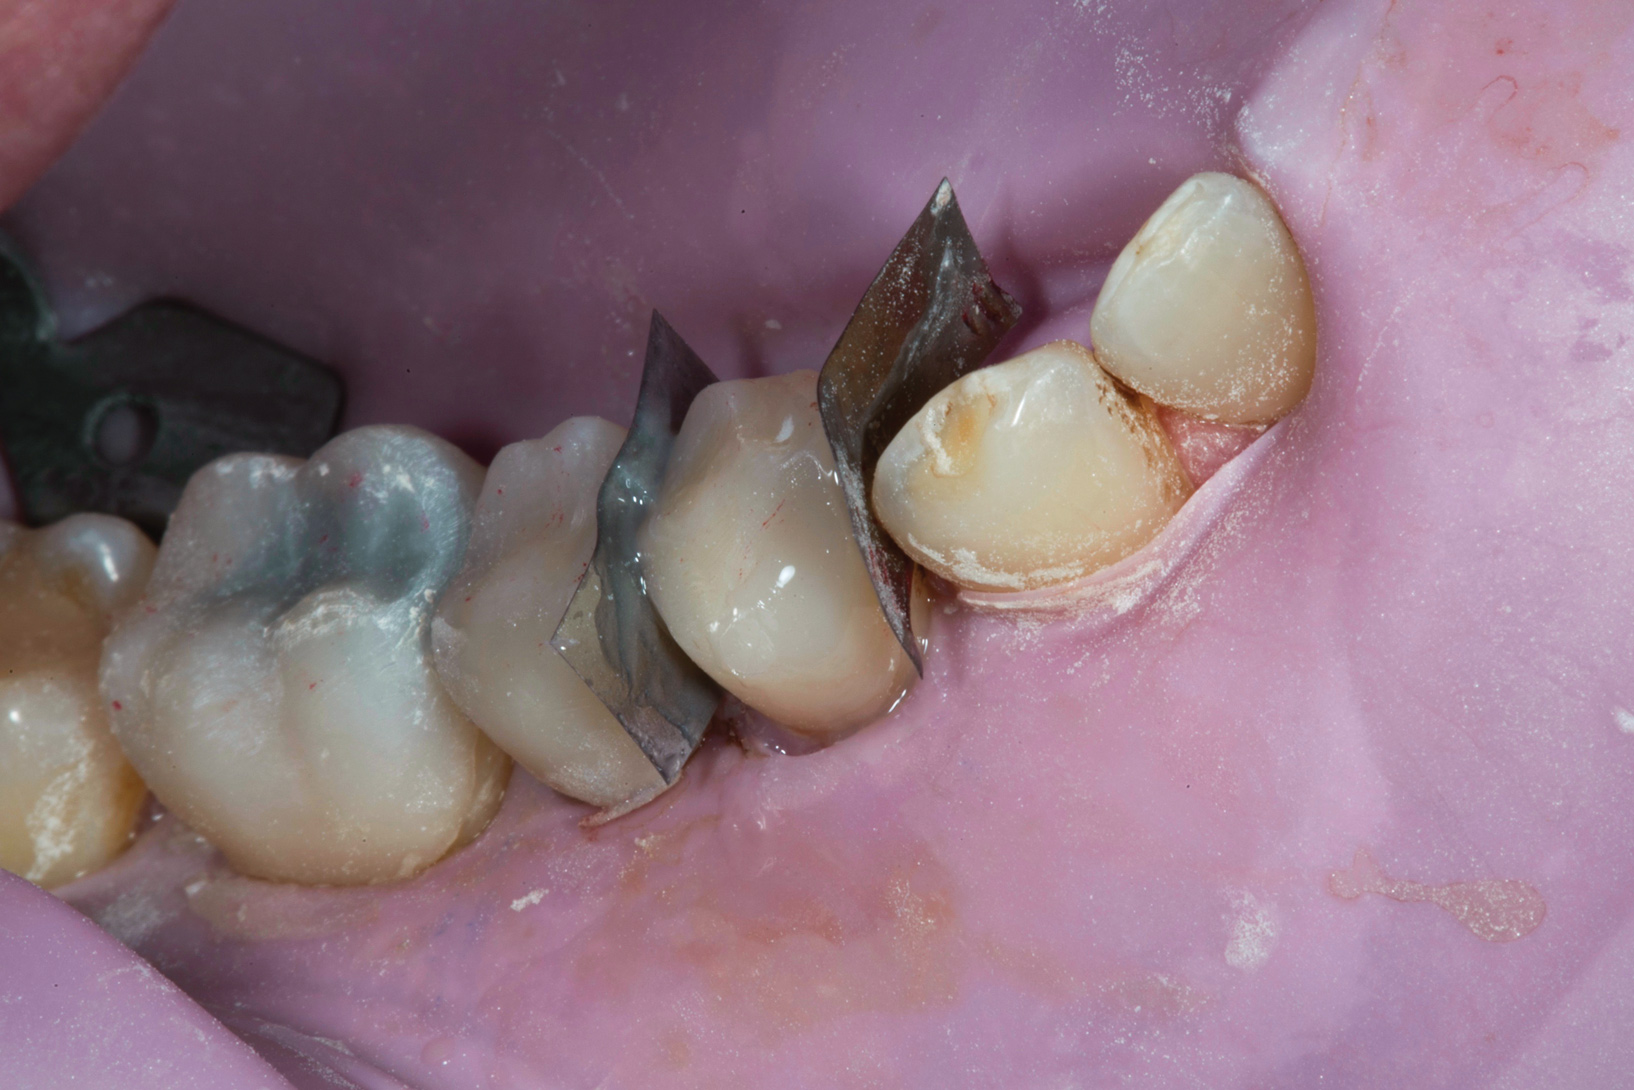

(6.) Fitting of prefabricated posterior units.

Figure 6

At the initial appointment, all of the patient's carious lesions were treated, and tooth No. 12 was fitted with a provisional crown made from a bis-GMA temporary material. At the next appointment, the patient's tissues were anesthetized, and the posterior teeth were isolated with a rubber dam in quadrants. The teeth were cleaned with air abrasion and etched with phosphoric acid. Studies have shown that air abrasion using 27 µm aluminum oxide at 40 psi greatly improves bond strength when compared with cleaning tooth surfaces using hand instruments, a slurry mixture of pumice and water, or air abrasion using 50 µm aluminum oxide at 40 psi.19 After silane and a bonding agent were applied, the onlays were loaded with a flowable composite and individually cemented (Figure 6). Minimal occlusal adjustments were then carried out to ensure simultaneous posterior contacts.